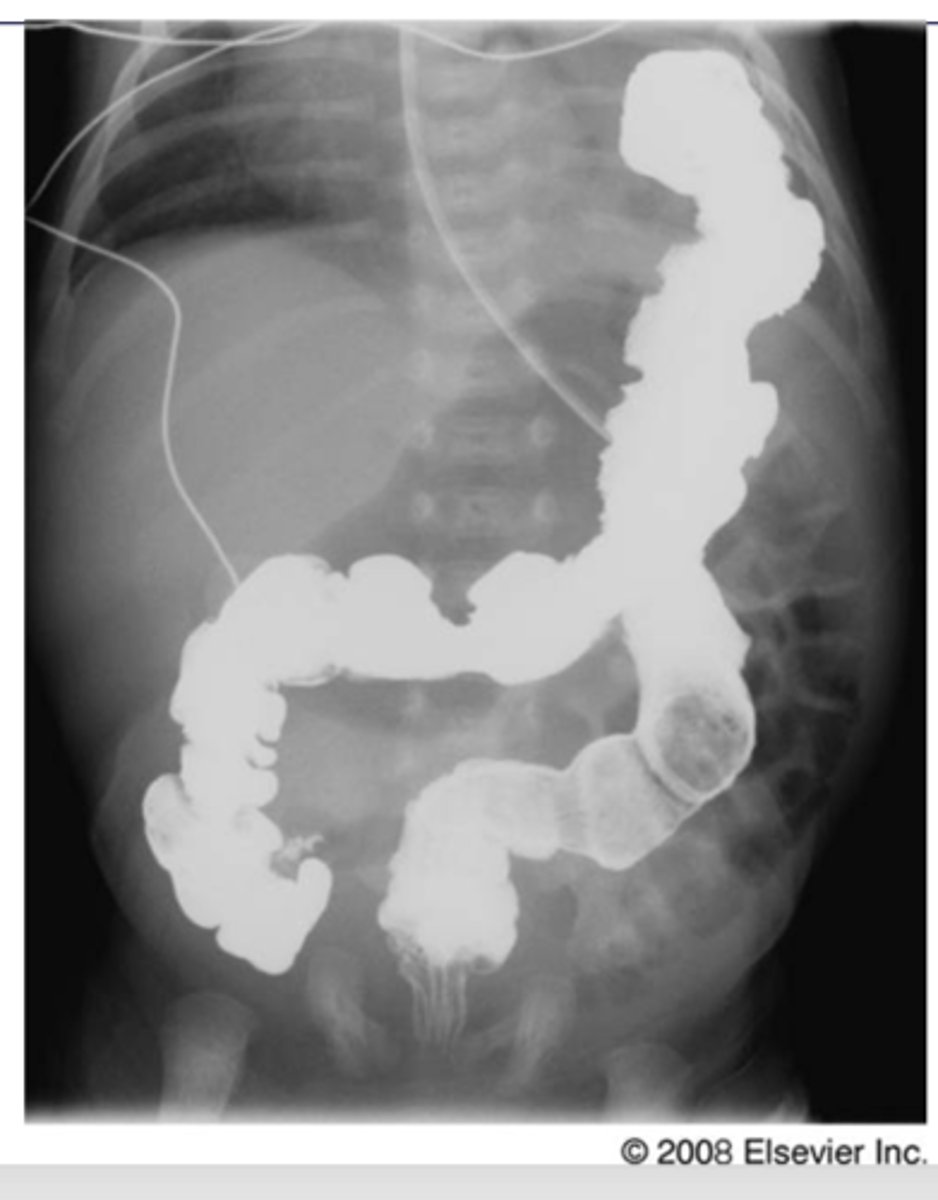

Diaphragmatic rupture

o Usually due to trauma – more common on the left side. Can be a post-op complication of upper GI surgery.

o Most common appearance is loops of bowel in the lower chest cavity (R lung in pic)

-Can cause mediastinal shift

Dx. What is the most common radiologic finding for this dz state?

<p>Dx. What is the most common radiologic finding for this dz state?</p>

Diaphragmatic rupture/hernia

-GI goes to area of least resistance

Dx

<p>Dx</p>